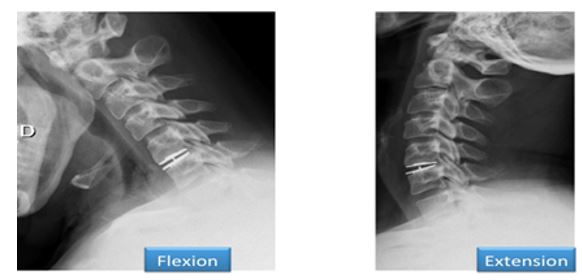

Prothèses discales